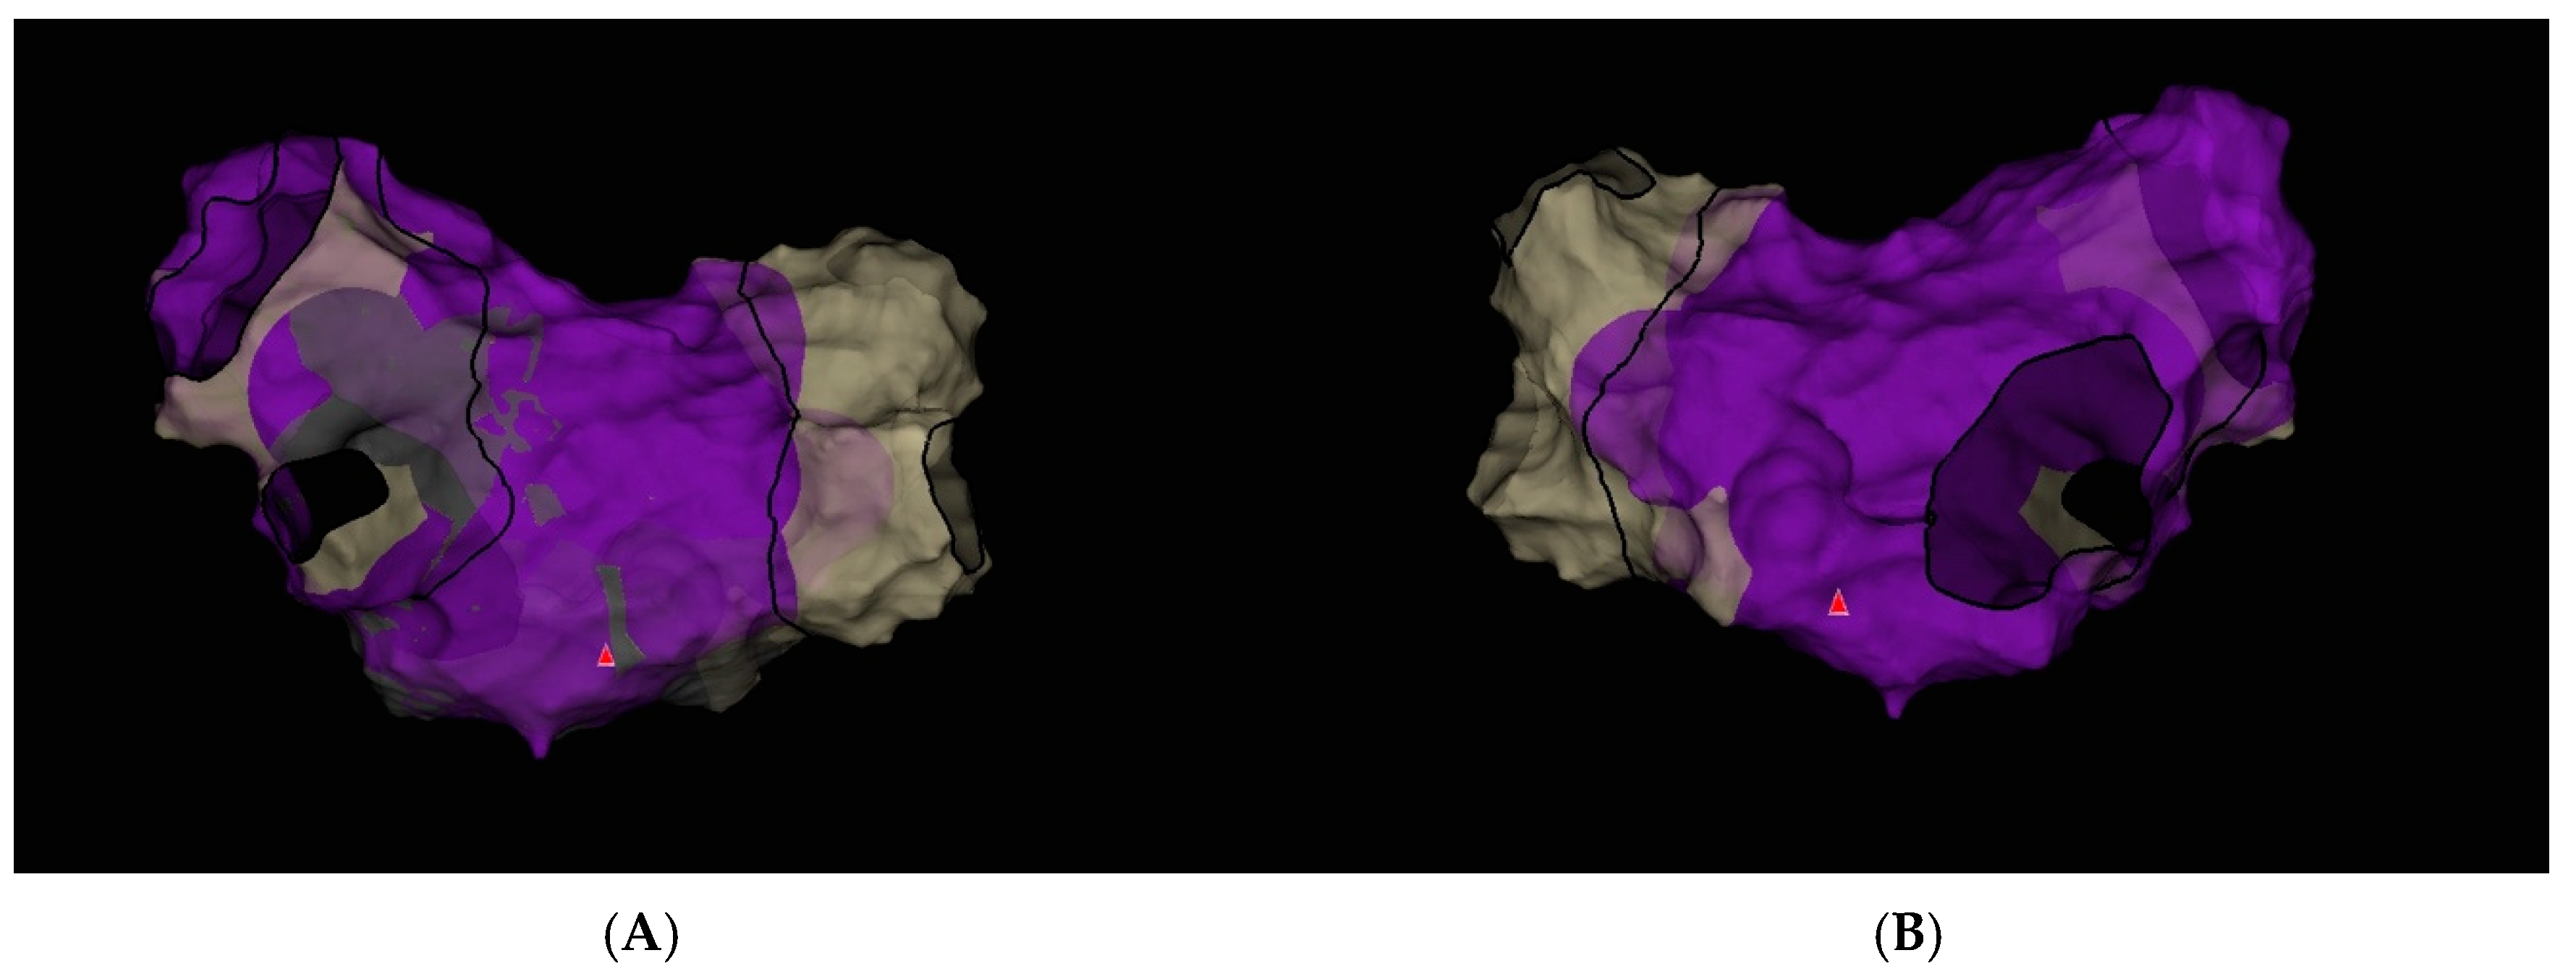

Transesophageal echocardiography (TEE) was performed to exclude the presence of intracardiac thrombi in the left atrium and left atrial appendage. Under local anesthesia, a diagnostic electrode was introduced via the right femoral vein into the coronary sinus (CS) and to the His bundle region in the right ventricle. A single transseptal puncture was performed, and a diagnostic Advisor HD Grid catheter was advanced into the left atrium through a steerable Agilis sheath. An electroanatomic map of the left atrium was created during ongoing AF (Figure 5).

In the final voltage map, no areas of low-voltage, high-amplitude potentials suggestive of additional arrhythmogenic substrate were identified (Figure 8).

Figure 5. Electroanatomic map of the left atrium during atrial fibrillation created using the Ensite X system (Advisor HD Grid mapping): (A) Posterior–Anterior view; (B) Anterior–Posterior view.

Figure 8. Electroanatomic map of the left atrium during sinus rhythm created using the Ensite X system (Advisor HD Grid mapping) after pulmonary vein isolation. (A) Posterior–Anterior view; (B) Anterior–Posterior view.